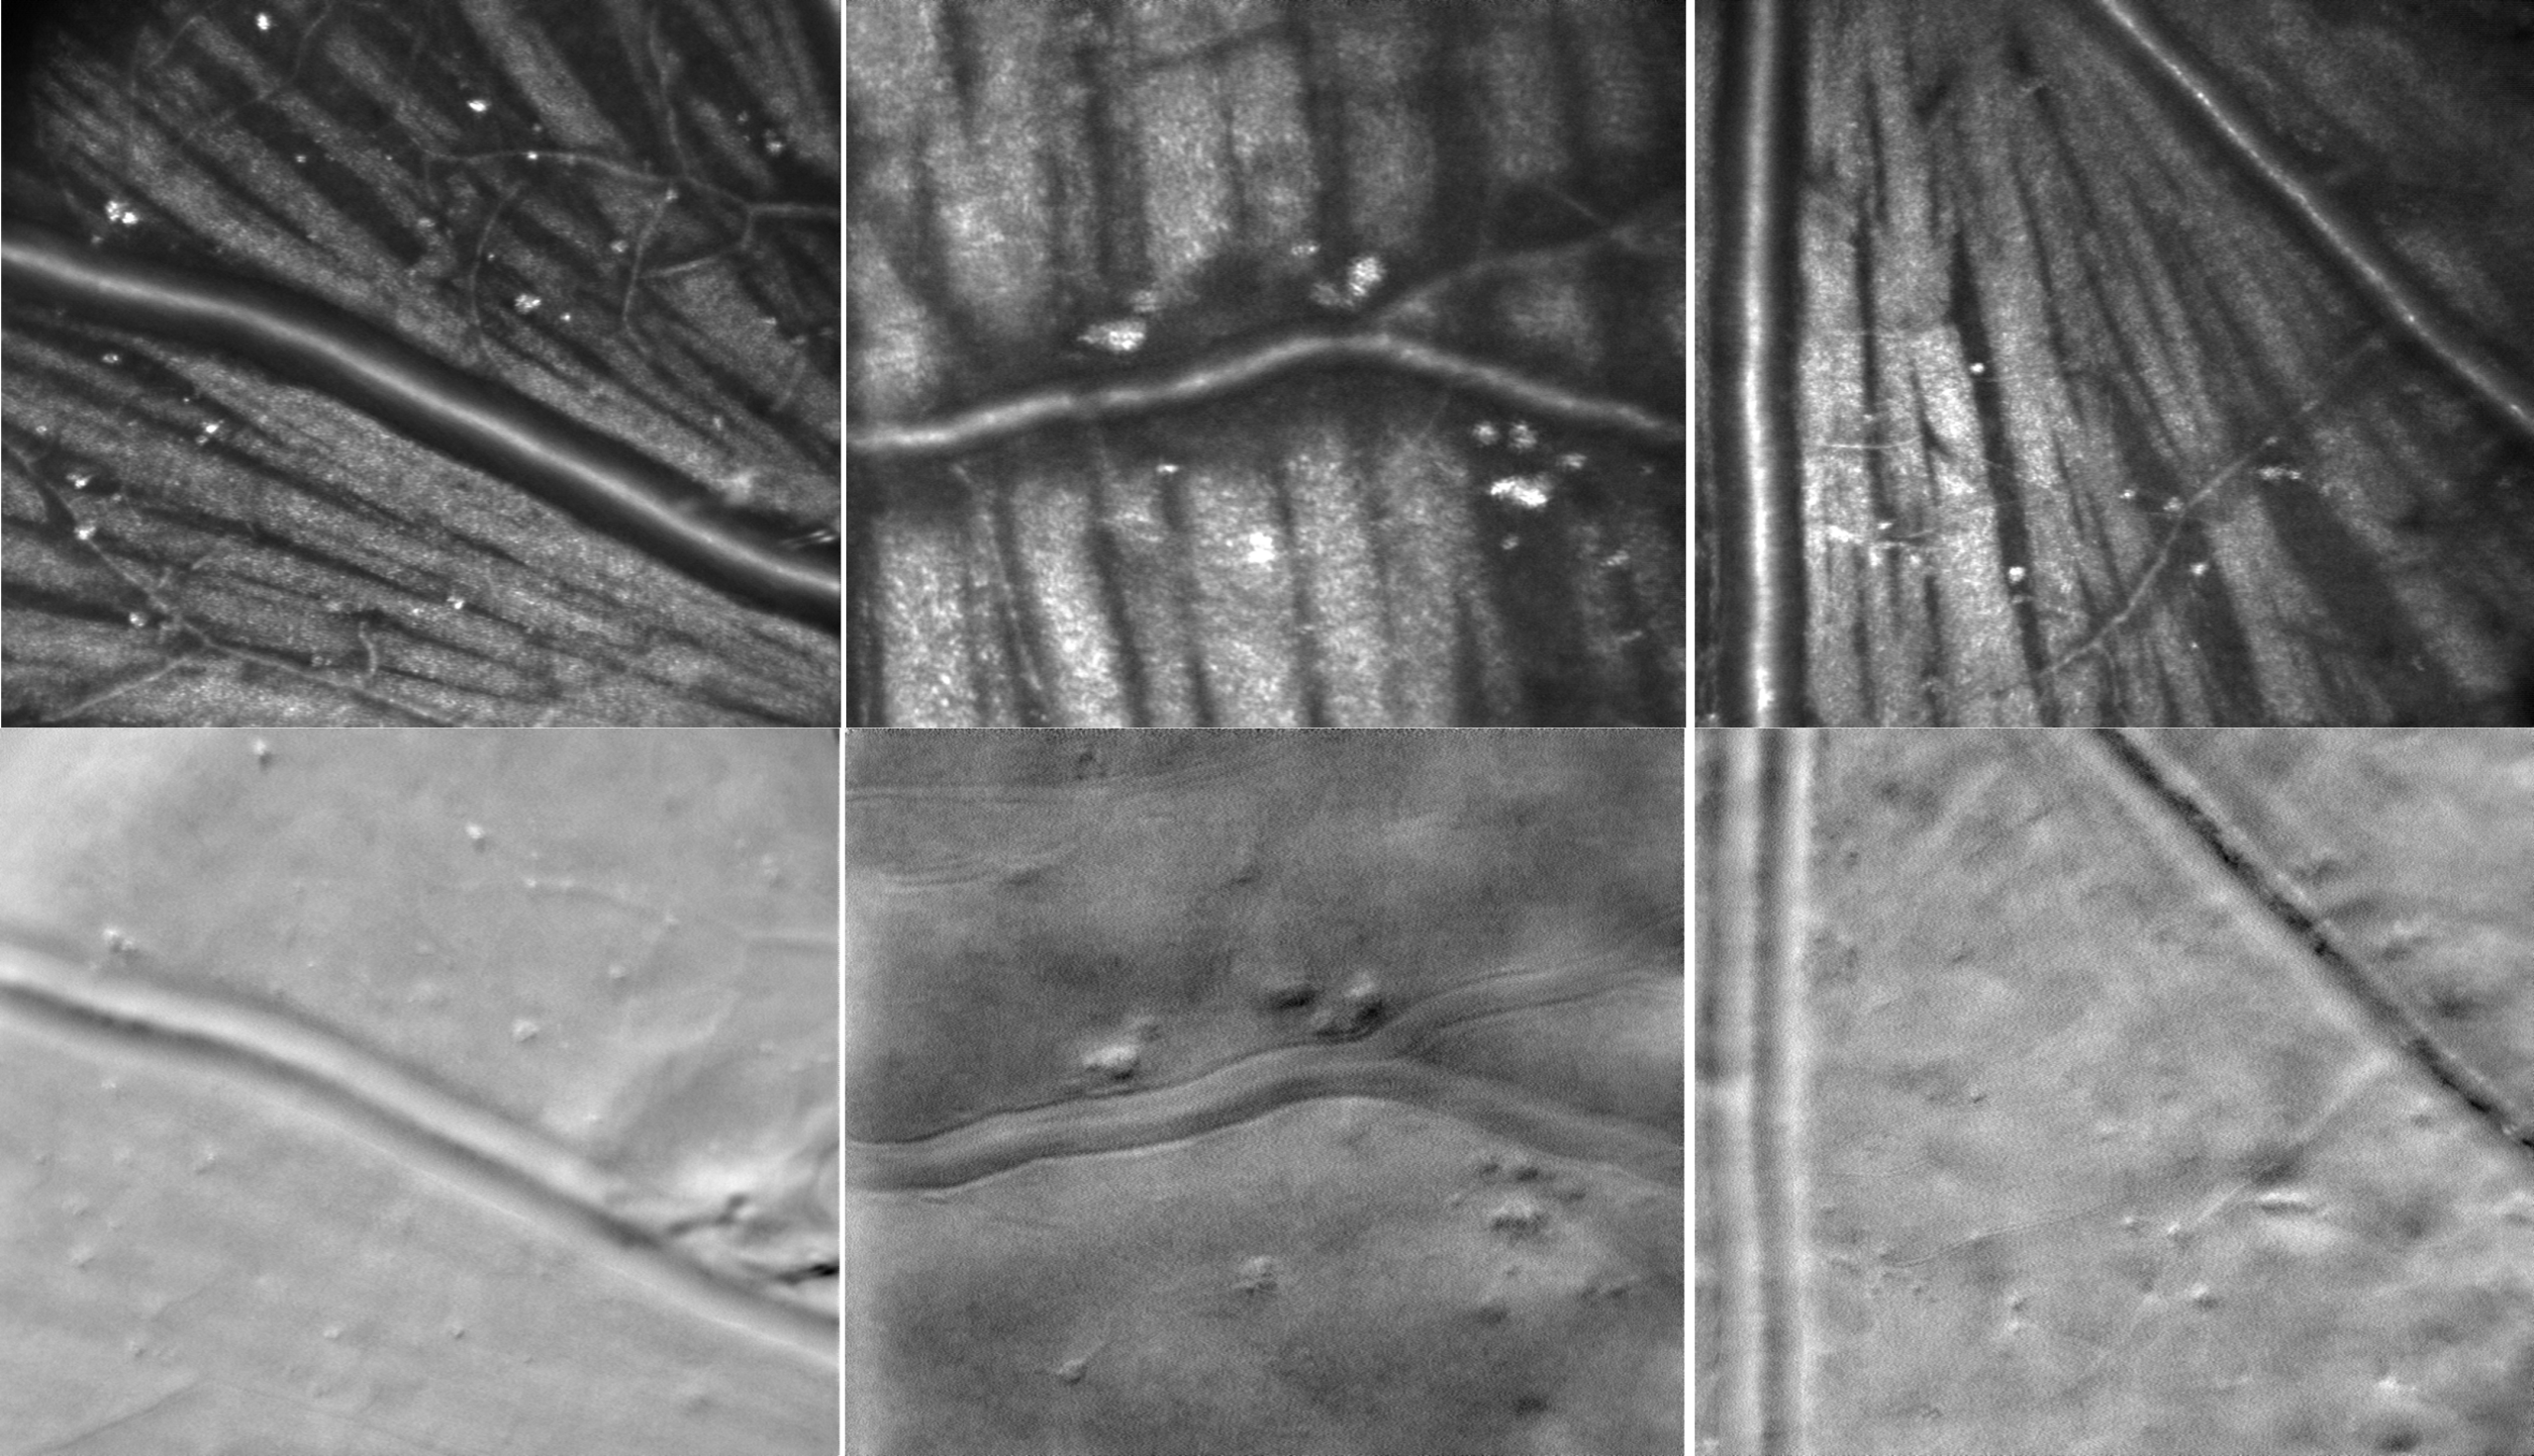

Phase gradient segmentation

“Cellular-Level Analysis of Retinal Blood Vessel Walls Based on Phase Gradient Images”, Diagnostics, 13(22), 3399, (2023)

Vessel wall disruptions visualized with phase gradient imaging